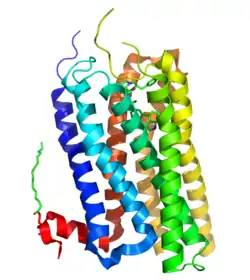

5-Hydroxytryptamine receptor 2B (5-HT2B) also known as serotonin receptor 2B is a protein that in humans is encoded by the HTR2B gene.[5][6] 5-HT2B is a member of the 5-HT2 receptor family that binds the neurotransmitter serotonin (5-hydroxytryptamine, 5-HT). Like all 5-HT2 receptors, the 5-HT2B receptor is Gq/G11-protein coupled, leading to downstream activation of phospholipase C.

The structure of the 5-HT2B receptor was resolved in a complex with the valvulopathogenic drug ergotamine.[26] As of 2009, few highly selective 5-HT2B receptor ligands have been discovered, although numerous potent non-selective compounds are known, particularly agents with concomitant 5-HT2C binding. Research in this area has been limited due to the cardiotoxicity of 5-HT2B agonists, and the lack of clear therapeutic application for 5-HT2B antagonists, but there is still a need for selective ligands for scientific research.[27]